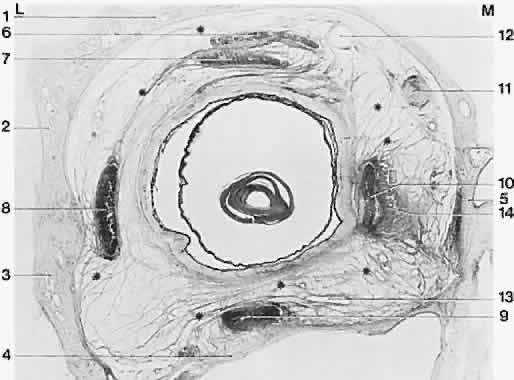

Fig. 12. Frontally sectioned histologic section (60 degree) of an adult right orbit, at a level in the orbit 3.2 mm anteriorly from the posterior pole of the eye. Asterisk, connective tissue septa; 1, frontal bone; 2, greater wing of sphenoid; 3, zygomatic bone; 4, maxilla; 5, ethmoid; 6, superior levator palpebrae muscle; 7, superior rectus muscle; 8, lateral rectus muscle; 9, inferior rectus muscle; 10, medial rectus muscle; 11, superior oblique muscle; 12, superior ophthalmic vein; 13, branches of inferior ophthalmic vein; 14, medial check ligament. Notice size difference of muscles; intermuscular membrane is well developed here. M, medial; L, lateral. Acidic fuchsin-picrin acid/van Gieson stain, original magnification × 2.5. (Koornef L: Arch Ophthalmol 95:1271, 1977.)